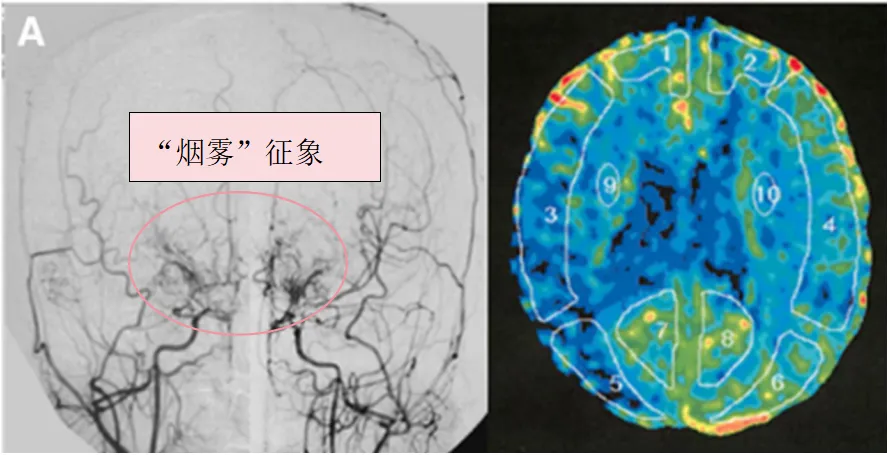

29岁女孩幸子(化名)被诊断患有烟雾病和格雷夫斯病(图1A),表现为左臂和左腿无力。检查发现幸子右侧额顶叶脑梗死(图1B),同时甲状腺功能检查提示游离甲状腺素(fT4)和游离三碘甲状腺原氨酸(fT3)、促甲状腺激素(TSH)和TSH受体抗体(TRAb)都明显升高(图2A,入院第20天)。

图1A:术前血管造影(双侧颈总动脉正位图)显示双侧颈内动脉末端有“烟雾血管狭窄征象”,双侧大脑中动脉(MCA)狭窄(左)。术前Xe-CT显示双侧MCA区域脑血流减少(右)